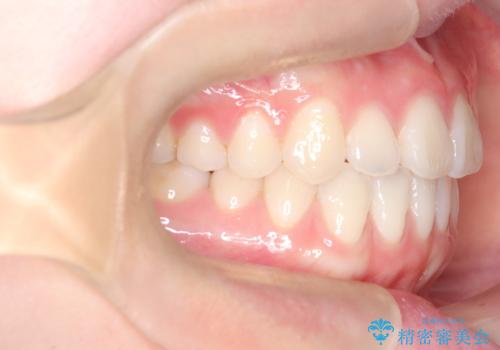

- 八重歯と、右上前歯(2番)が下の歯より内側に入っている反対咬合を気にされてご来院されました。精密な検査の結果、八重歯と反対咬合を同時に改善するためには、歯列全体にスペースを確保する必要があると判明。患者様のご希望から、透明で目立たないインビザライン(マウスピース矯正)による治療計画を立案しました。奥歯全体を奥へ動かす遠心移動でスペースを作り、これらの複雑な問題を一括で解消することを目指します。

今回の矯正治療では、透明なマウスピース型の装置インビザラインを使用しました。治療は、緻密なデジタル計画に基づき、奥歯から順に歯列全体を後方へ移動させる遠心移動を実施。これにより、八重歯を正しい位置に並べるためのスペースを確保しました。同時に、右上の2番を前方に誘導することで反対咬合を解消。結果として、抜歯することなく八重歯と反対咬合という複数の問題が改善され、機能的で美しい歯並びを獲得していただけました。